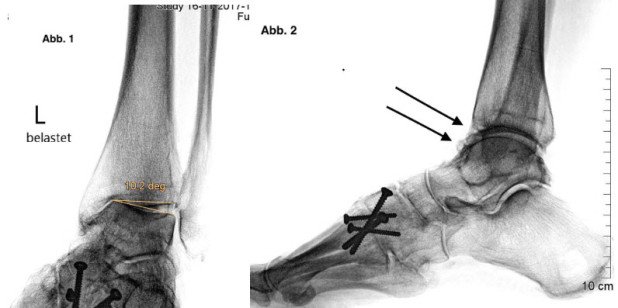

Ursache der jetzigen Schmerzen beim Gehen war eine fortgeschrittene Arthrose im oberen Sprunggelenk bei Schrägstellung des Sprungbeins (Talus). Diese Fehlstellung hatte sich in Folge eines zu laxen Aussenbandapparates – möglicherweise Folge einer Bandverletzung in jüngeren Jahren – entwickelt. Mittels der eingeleiteten konservativen Therapiemassnahmen konnte sich die Patientin für gut ein halbes Jahr einigermassen behelfen. Letztlich blieb aufgrund der zunehmenden Schmerzen mit inakzeptabler Einschränkung der Gehzeit nur noch die Möglichkeit eines operativen Eingriffs. Bei sehr guter Beweglichkeit des betroffenen Gelenkes, die es zu erhalten galt, wurde gemeinsam mit der Patientin entschieden, ein Kunstgelenk einzusetzen. Das Kunstgelenk erlaubt den Erhalt der Gelenkfunktion und damit gegenüber der Versteifung den Vorteil, dass die Nachbargelenke vor einem übermässigen Verschleiss geschützt werden.

Abb. 2: Arthrose mit auffälliger Schrägstellung des Sprungbeins. Die innere Schulter des Sprungbeins hat Kontakt mit der Gelenkfläche des Schienbeins. Dies verursacht Schmerzen bei jedem Schritt. Der Gelenkspalt ist auf der Aussenseite noch gut erhalten.